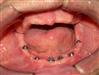

Reabilitação estética multidisciplinar, envolvendo as áreas de ortodontia, cirurgia oral menor, tratamento com enxerto ósseo em bloco, implantes, próteses convencionais, facetas e próteses sobre implantes.

Reabilitação estética  multidisciplinar realizada por clínico geral, constando de duas fases: Tratamento ortodôntico e tratamento protético.

Caso de reabilitação estética com implantes de carregamento imediato.